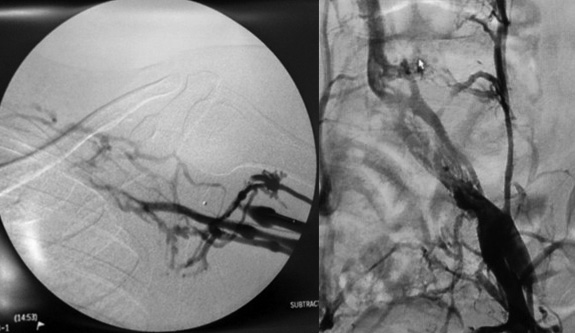

Artérias são os vasos responsáveis por levar o sangue do coração para cada órgão e tecido de nosso corpo, exercendo função de irrigação e nutrição aos órgãos e tecidos…

Aneurismas Arteriais

caracterizados pela dilatação de uma ou mais artérias, excedendo em 50% o diâmetro normal do vaso. Dentre as suas principais causas encontram-se o tabagismo….